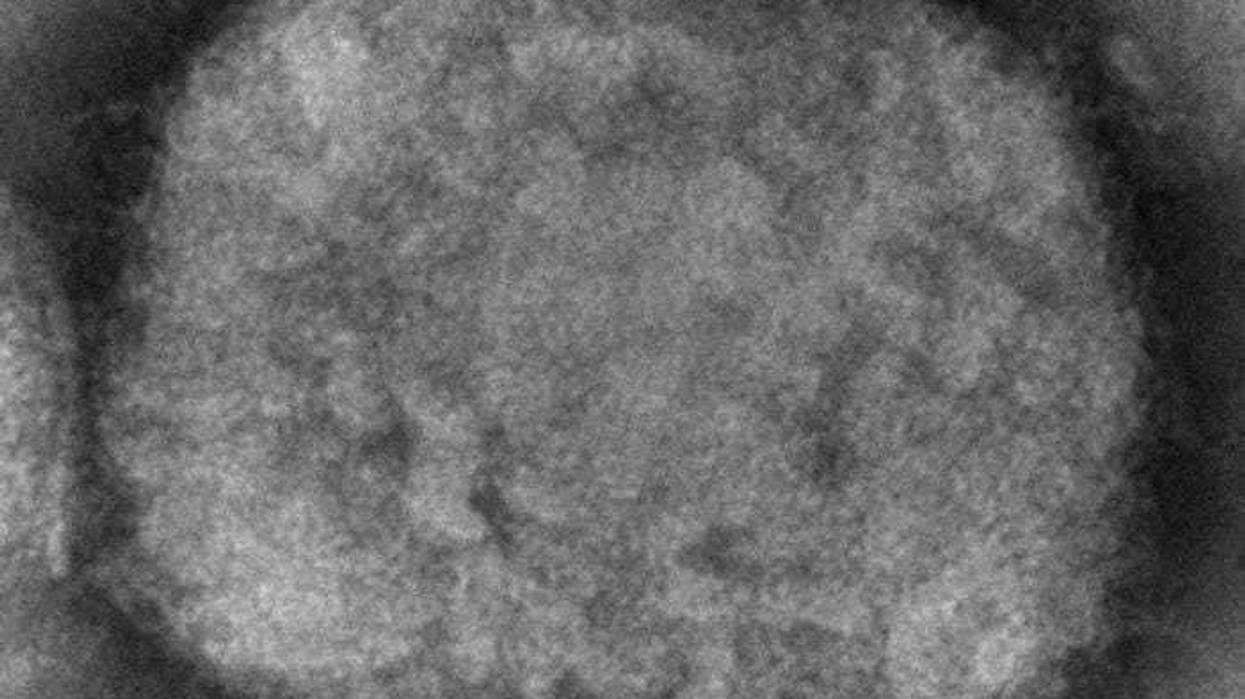

NEW YORK (AP) — Two children have been diagnosed with monkeypox in the U.S., health officials said Friday.

Monkeypox is endemic in parts of Africa, but this year more than 15,000 cases have been reported in countries that historically don't see the disease. In the U.S. and Europe, the vast majority of infections have happened in men who have sex with men, though health officials have stressed that anyone can catch the virus.